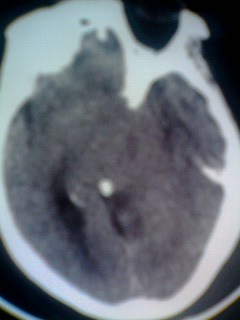

女。65岁头疼,多发硬化病史5年,近十余天加重

巨大囊性占位,白质水肿确不明显,定性?

囊实性占位,考虑胶质瘤可能性大,建议增强.

北京天坛,结论:多发硬化